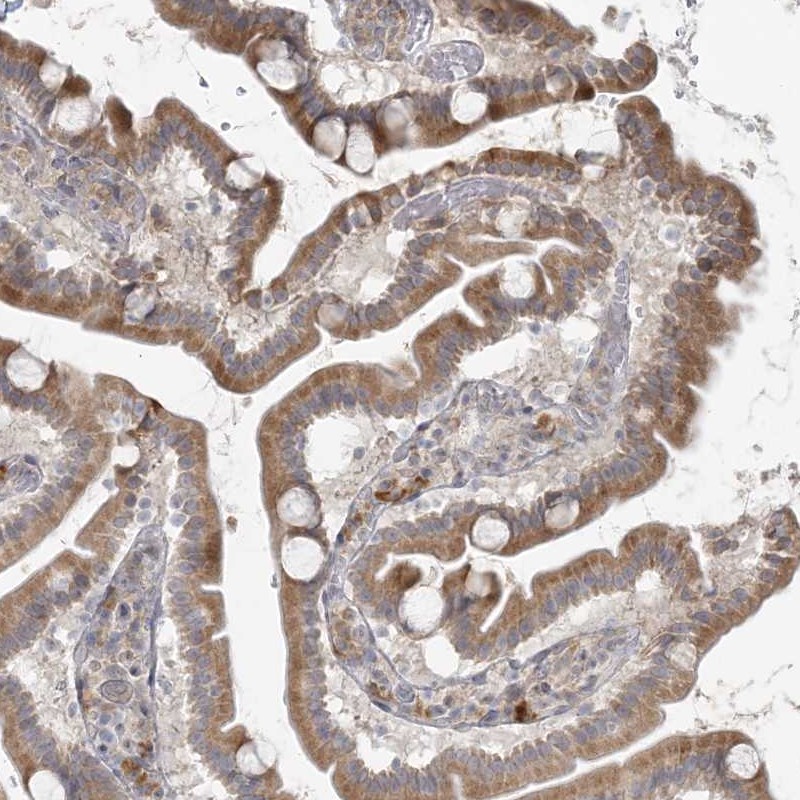

Immunohistochemical staining of human duodenum shows moderate cytoplasmic positivity in glandular cells.